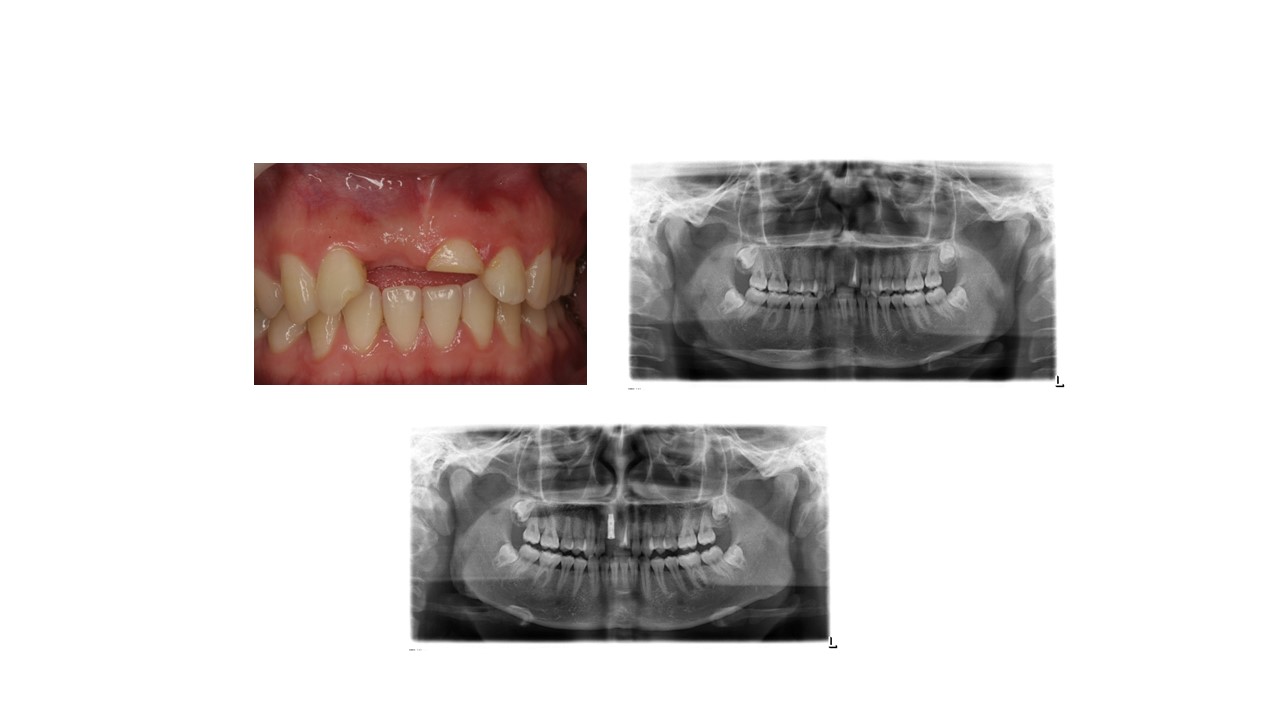

种植科普